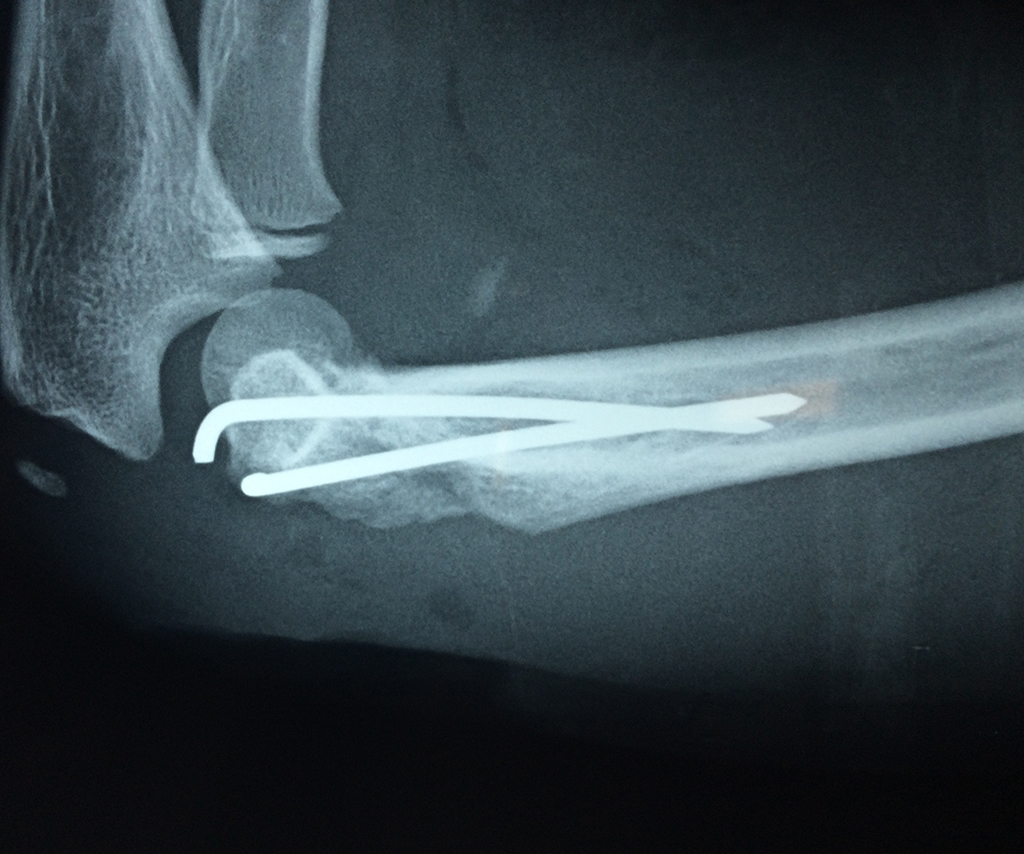

En el lenguaje común se le da el nombre de codo a la parte posterior y prominente situada en la unión del brazo con el antebrazo.